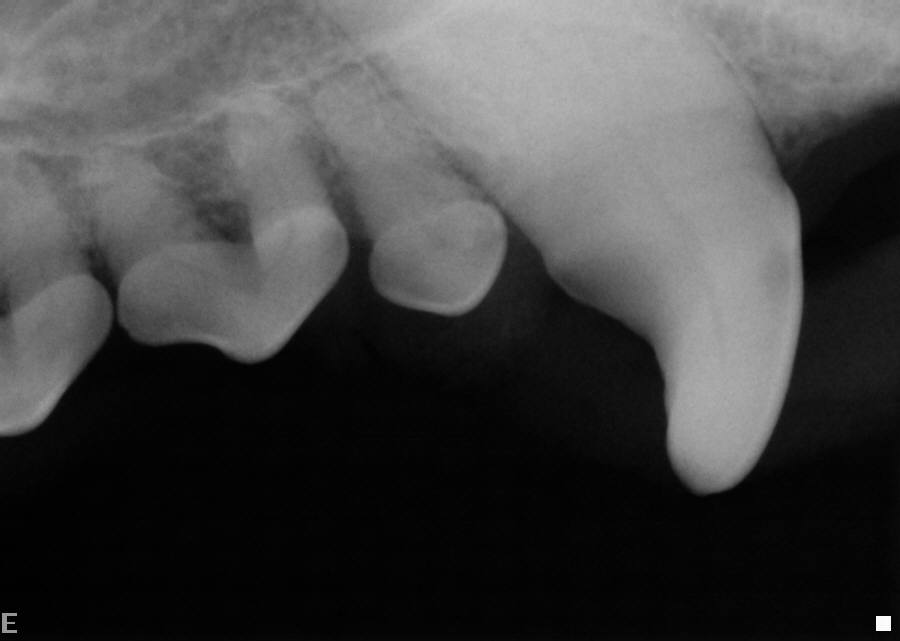

Dental X-ray Left Mandibular